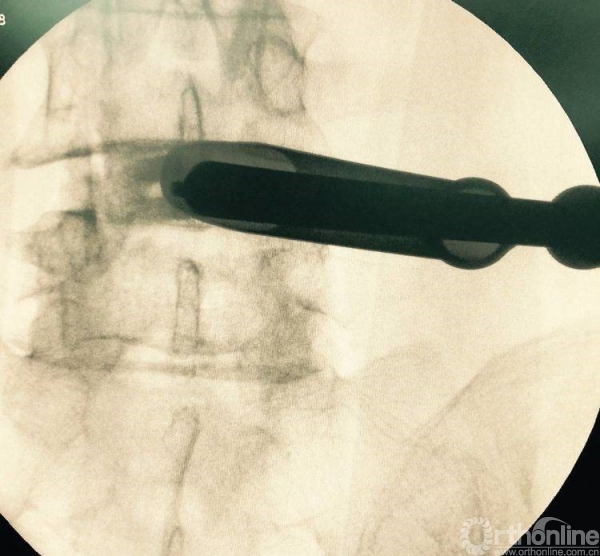

消毒前,给予椎间隙定位

放入减压工作通道

处理干净椎间隙后,透视观察工作通道的位置,镜下看到前纵韧带的纤维交错位置,为减压充分标志

正位观察透视,判断是否处理至边缘